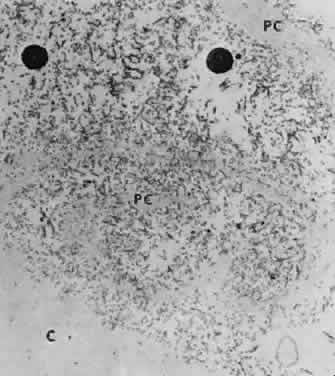

Accumulation of exfoliative material may be detected histopathologically throughout the anterior segment to include the lens, iris, trabecular structures, conjunctiva, ciliary body, and zonules. The deposition of fibrillar eosinophilic material on the anterior lens capsule is the classic histopathologic feature of XFS (Fig. 9). Ultrastructural studies also indicate some degree of actual exfoliative changes or peeling of the anterior lens capsule74 (Figs. 10 and 11). In addition, Ashton and associates describe a degenerative band containing exfoliative material within the inner half of the lens capsule.5 Bertelsen and coworkers independently noted projection of coarse fibrils from the lens surface into the deep portion of the lens capsule to form an amorphous layer of the lens capsule between the lens epithelium and normal lens capsule.6 Thus, studies indicate that exfoliative material accumulates on the anterior lens surface but also that the lens capsule itself may be involved, and that the underlying epithelial layer may at least partially contribute to the production of the exfoliative material.

Fig. 10. Scanning electron micrograph showing layer of anterior lens capsule and exfoliative material (PC) peeling back from rest of capsule. Asterisks indicate exfoliative vegetations (× 5340). (Dark AJ, Streeten BW, Cornwall CC: Pseudoexfoliative disease of the lens: A study in electron microscopy and histochemistry. Br J Ophthalmol 61:466,1977)

Fig. 11. Transmission electron micrograph of peeling lens capsule (PC) rolled up in spiral, enclosing masses of exfoliative fibers and two melanin granules. C, main capsule (× 14,600). (Courtesy of Dr. Barbara Streeten)

NATURE OF EXFOLIATIVE MATERIAL

Exfoliative material consists of an irregular meshwork of fibers composed of fibrillar subunits.74,92 Masses of these fibers correspond to the material seen clinically (see Fig. 10). The individual fibrils, which measure 6 to 8 nm in diameter and exhibit cross-banding at 10- to 12-nm intervals, are hypothesized to consist of macromolecules with a protein backbone and polysaccharide side chains.93–95 In contrast to collagen, the amino acid content of exfoliative material lacks hydroxyproline.96 Ringvold and Husby noted histochemical, immunologic, and ultrastructural features that led them to classify exfoliative material as an amyloid-like substance.97 Repo and associates note Congo red-positive staining for amyloid in the vessel walls of 7 of 13 iris specimens from exfoliation patients and believe that these findings support the theory that XFS is associated with amyloid.59 Immunohistochemical studies by other investigators show heparin sulfate and chondroitin sulfate proteoglycans, laminin, entactin/nidogen, fibronectin, and amyloid P protein to be components of exfoliation material.98,99 Schlötzer-Schrehardt and coworkers suggest that the material may be an expression of a disordered extracellular matrix synthesis.98